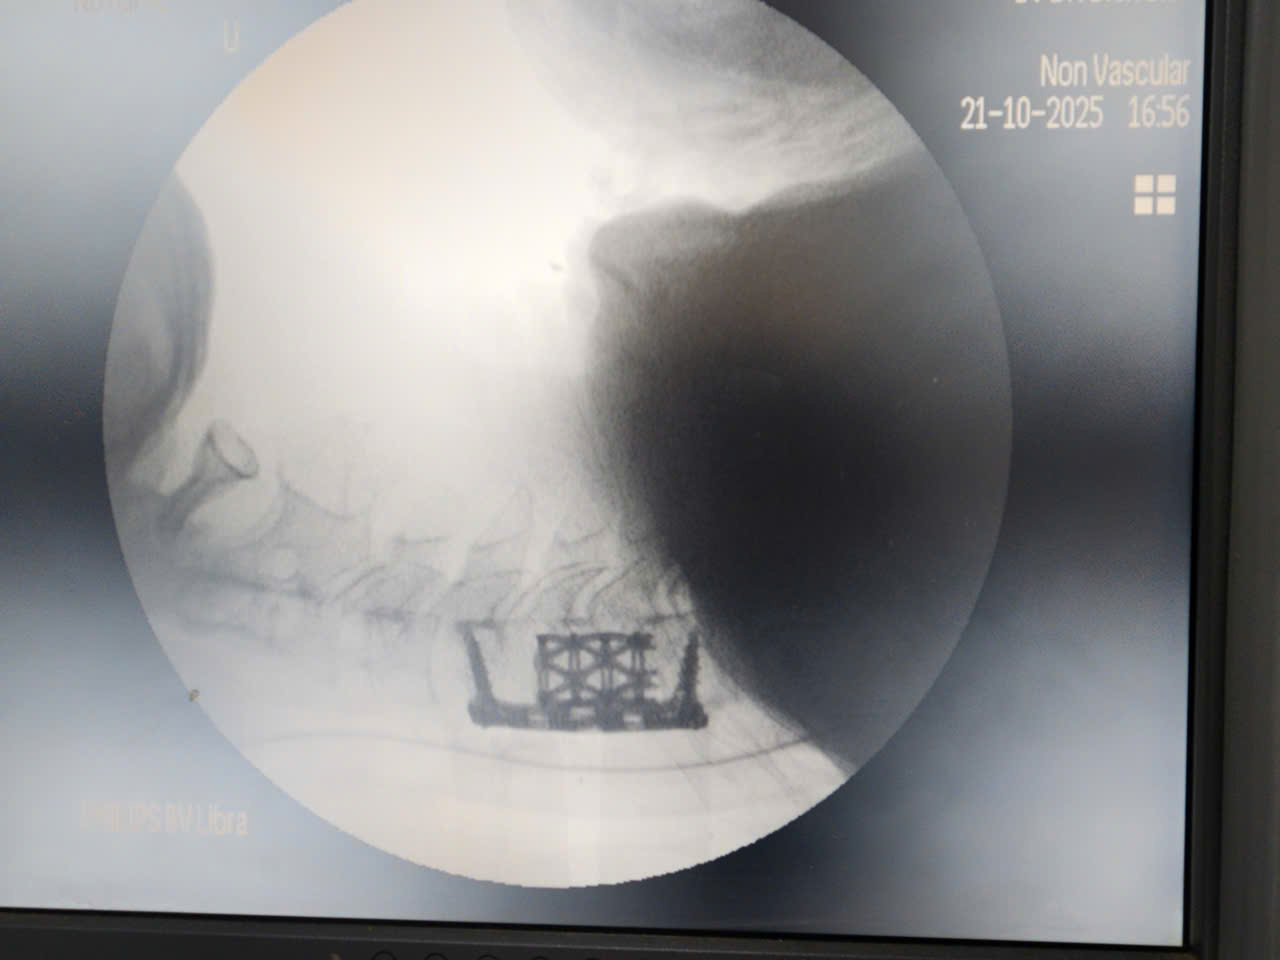

- Sử dụng Hệ thống C-Arm: Đảm bảo kiểm soát hình ảnh X-quang trực tiếp trong suốt quá trình mổ, cho phép ê-kíp xác định chính xác vị trí và góc độ khoan, đặt vật liệu, tránh tối đa tổn thương thần kinh và mạch máu.

Khoang đốt sống được thay thế bằng lồng Titan (Titanium Cage)

- Kỹ thuật thay thế Đốt sống Vỡ vụn: Các mảnh vỡ của thân đốt sống C5 được loại bỏ cẩn thận. Khoang đốt sống được thay thế bằng lồng Titan (Titanium Cage), một vật liệu nhân tạo có độ tương thích sinh học và độ cứng cơ học cao, nhằm tái tạo chiều cao thân đốt sống và giải phóng hoàn toàn chèn ép tủy.